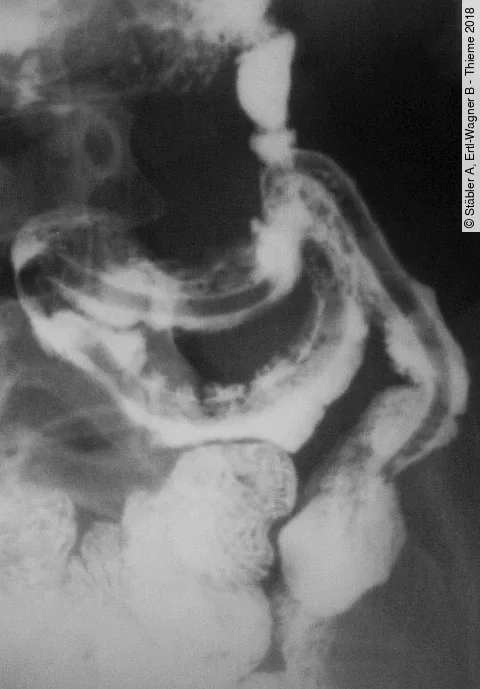

Rezidivierende ödematöse Veränderungen im Gastrointestinaltrakt, die zu einer Obstruktion und zum (Sub)Ileus mit rezidivierendem Erbrechen/Reflux oder Stuhlverhalt führen. Welche Ursachen sind möglich?

Rezidivierende ödematöse Veränderungen im Gastrointestinaltrakt, die zu einer Obstruktion und zum (Sub)Ileus mit rezidivierendem Erbrechen/Reflux oder Stuhlverhalt führen. Diese Ursachen sind möglich.